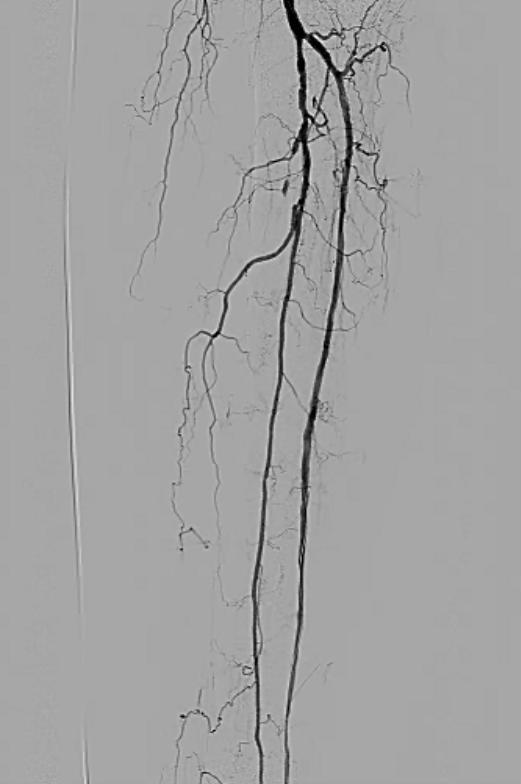

There was a severe stenosis of the left tibioperoneal trunk (Figure 2) and single vessel runoff to the foot via the left peroneal artery (Figure 3):